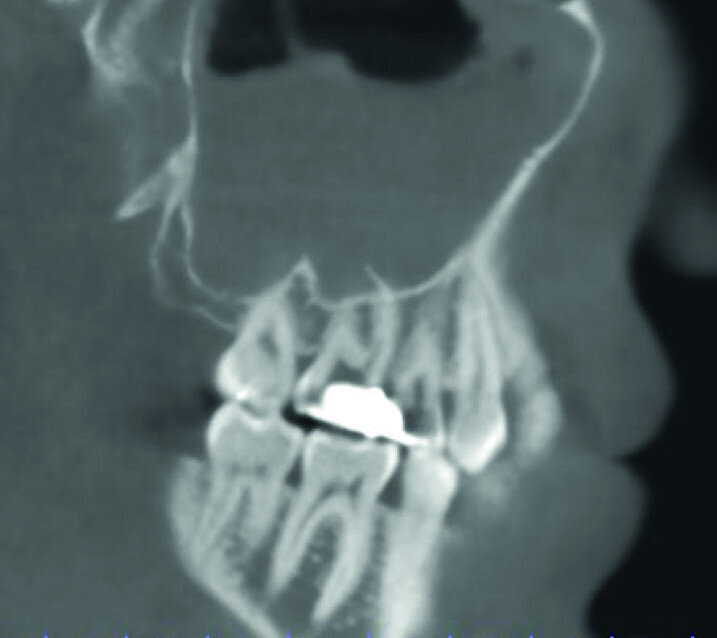

A patient was referred to the office with problems related to separated files. He was a pilot and was complaining of pus draining from his nose when flying. From the preoperative radiograph (Fig. 1), it was clear that there were two separated file fragments in the mesial canals and one cone passing beyond the apex in the palatal root. I requested an iCAT scan, and from this, the left sinus was clearly almost full with inflammatory fluid (Fig. 2) and the cone in the palatal canal was clearly emerging into the sinus. We could also see the two separated files in the two mesial canals clearly in the MPR view (Figs. 3 & 4), as well as another file entering the sinus and not attached to the canal (Fig. 5). We could see the file using different filters (Figs. 6–9), as well as the inflammation inside the sinus and the separated file. We additionally gained a better idea of the location of the cone protruding from the palatal canal into the sinus.

The treatment plan was to try to solve it with a conventional approach and if necessary to perform microsurgery to save the tooth. With the help of H-files, I managed to retrieve the cone from the palatal root, but the files inside the mesial root were impossible to bypass or even to reach with ultrasonic tips. I decided not to overdo it in order to avoid creating an additional problem, like perforating the canal, and decided to seal the canals (Fig. 10). A surgical approach was immediately taken for the mesial canals, cutting 3 mm of the mesial root using the Impact Air handpiece (SybronEndo), and this gave me a direct view of the Schneiderian membrane, where the third file was barely hanging (Figs. 11 & 12). I managed to delicate grab it and to remove it (Fig. 13). Figure 14 shows the postoperative situation, after performing retrograde preparation of the mesial canals.